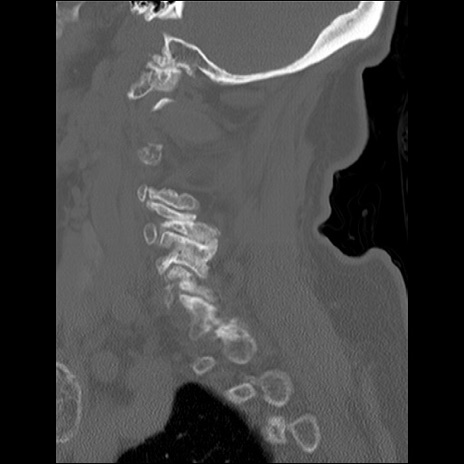

症例48 頚椎CT(矢状断像)

頚椎CT